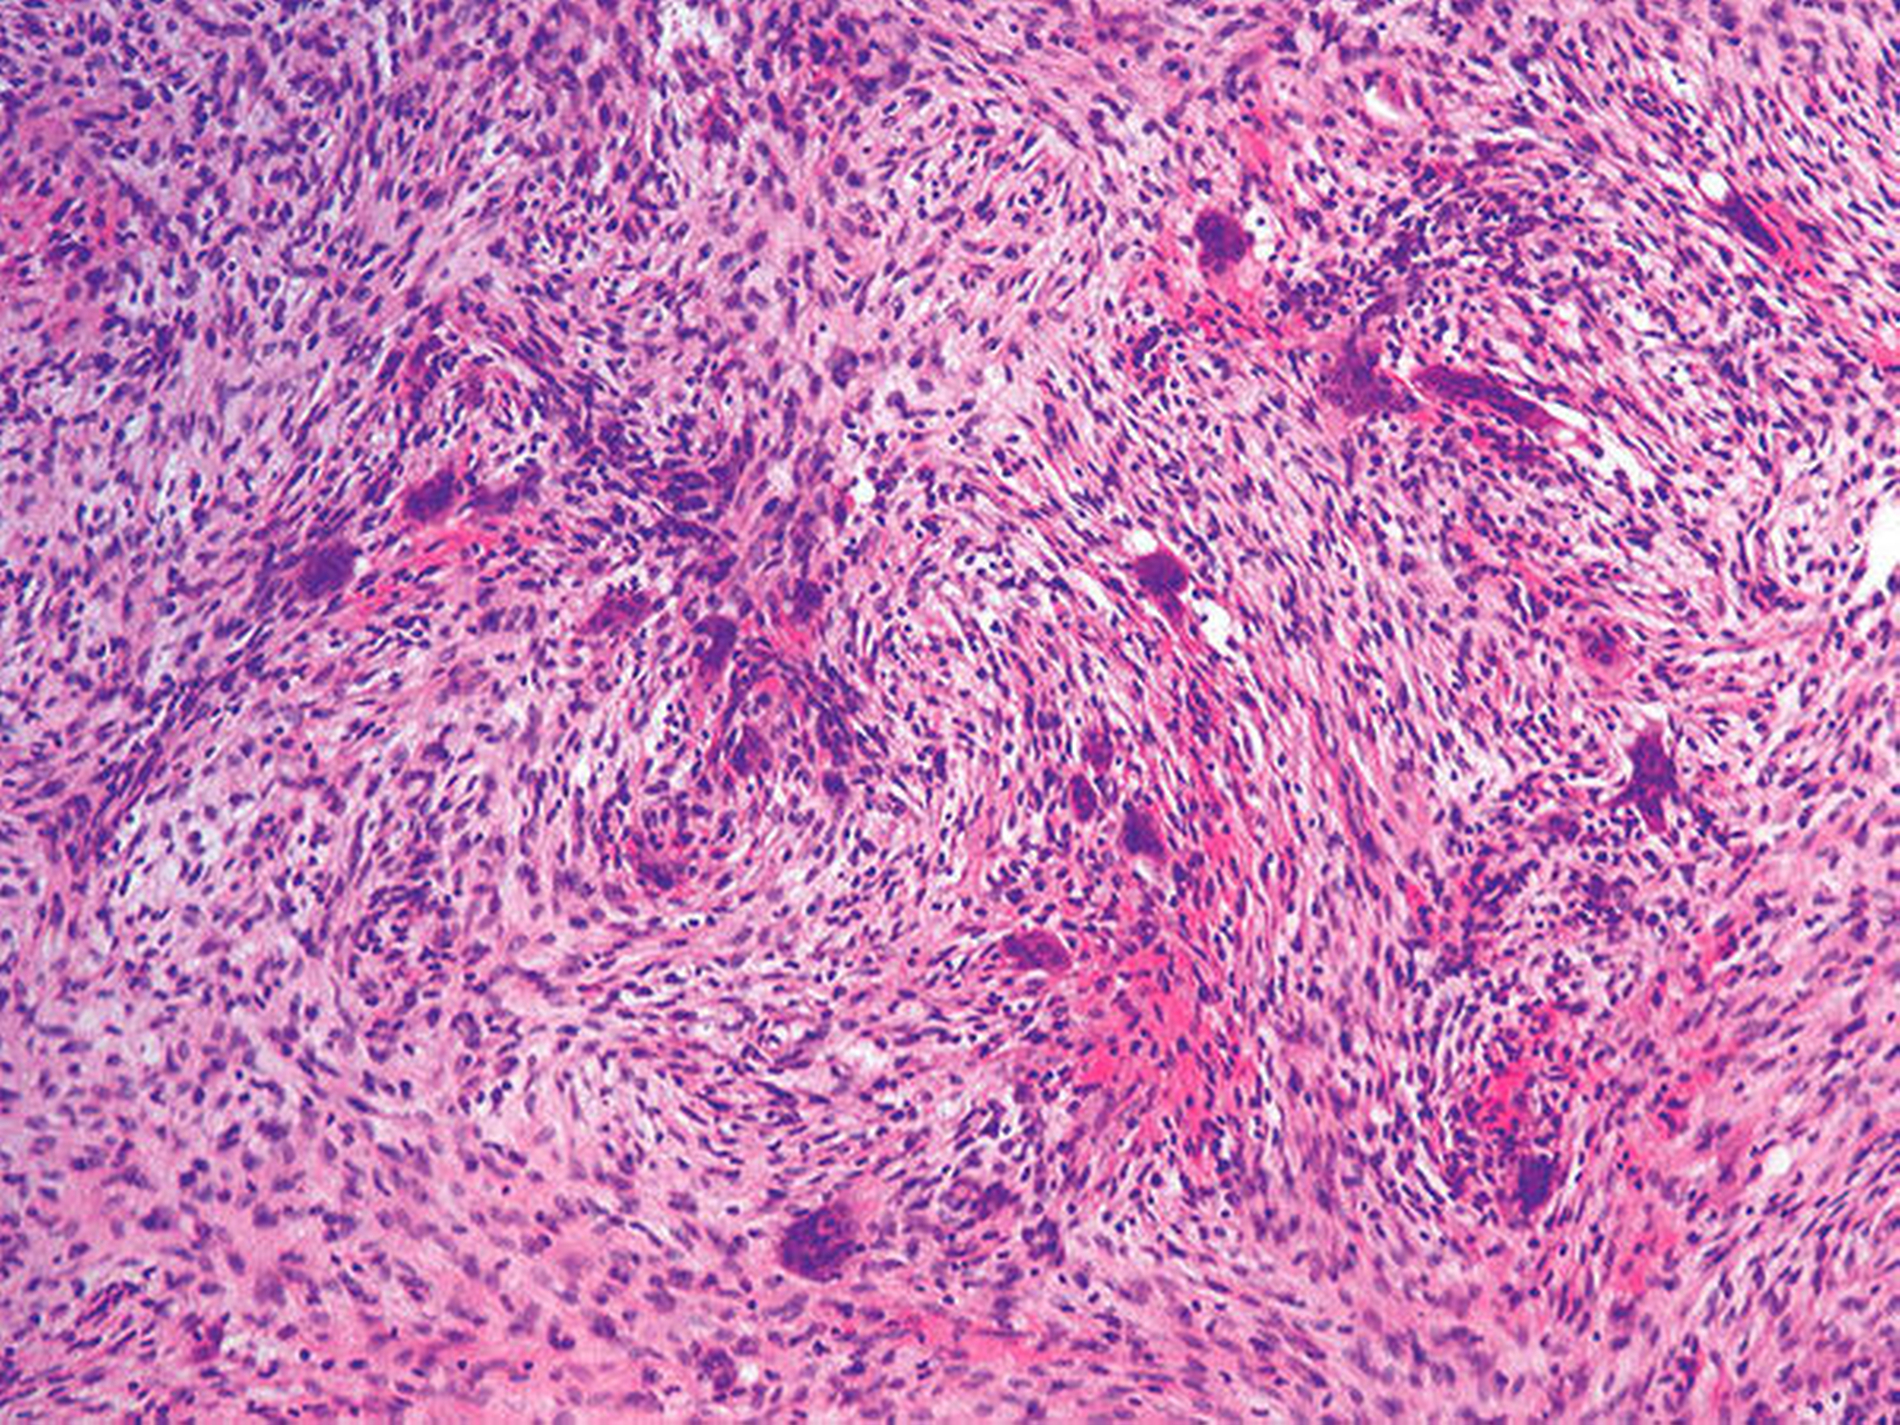

In Basel wurde die Diagnose eines zentralen Riesenzellgranuloms bestätigt. Histologisch zeigte sich die klassische Konstellation einer lobulär gegliederten und teilweise stori‧formen Proliferation monomorpher Spindel‧zellen mit eingeschlossenen und unregelmäßig verteilt gelegenen mehrkernigen Riesen‧zellen und Siderophagen (Abbildung 6) [Driemel et al., 2006]. Unter Berücksich‧tigung eines normwertigen Parathormons wurde die Diagnose eines zentralen Riesenzellgranuloms festgelegt.